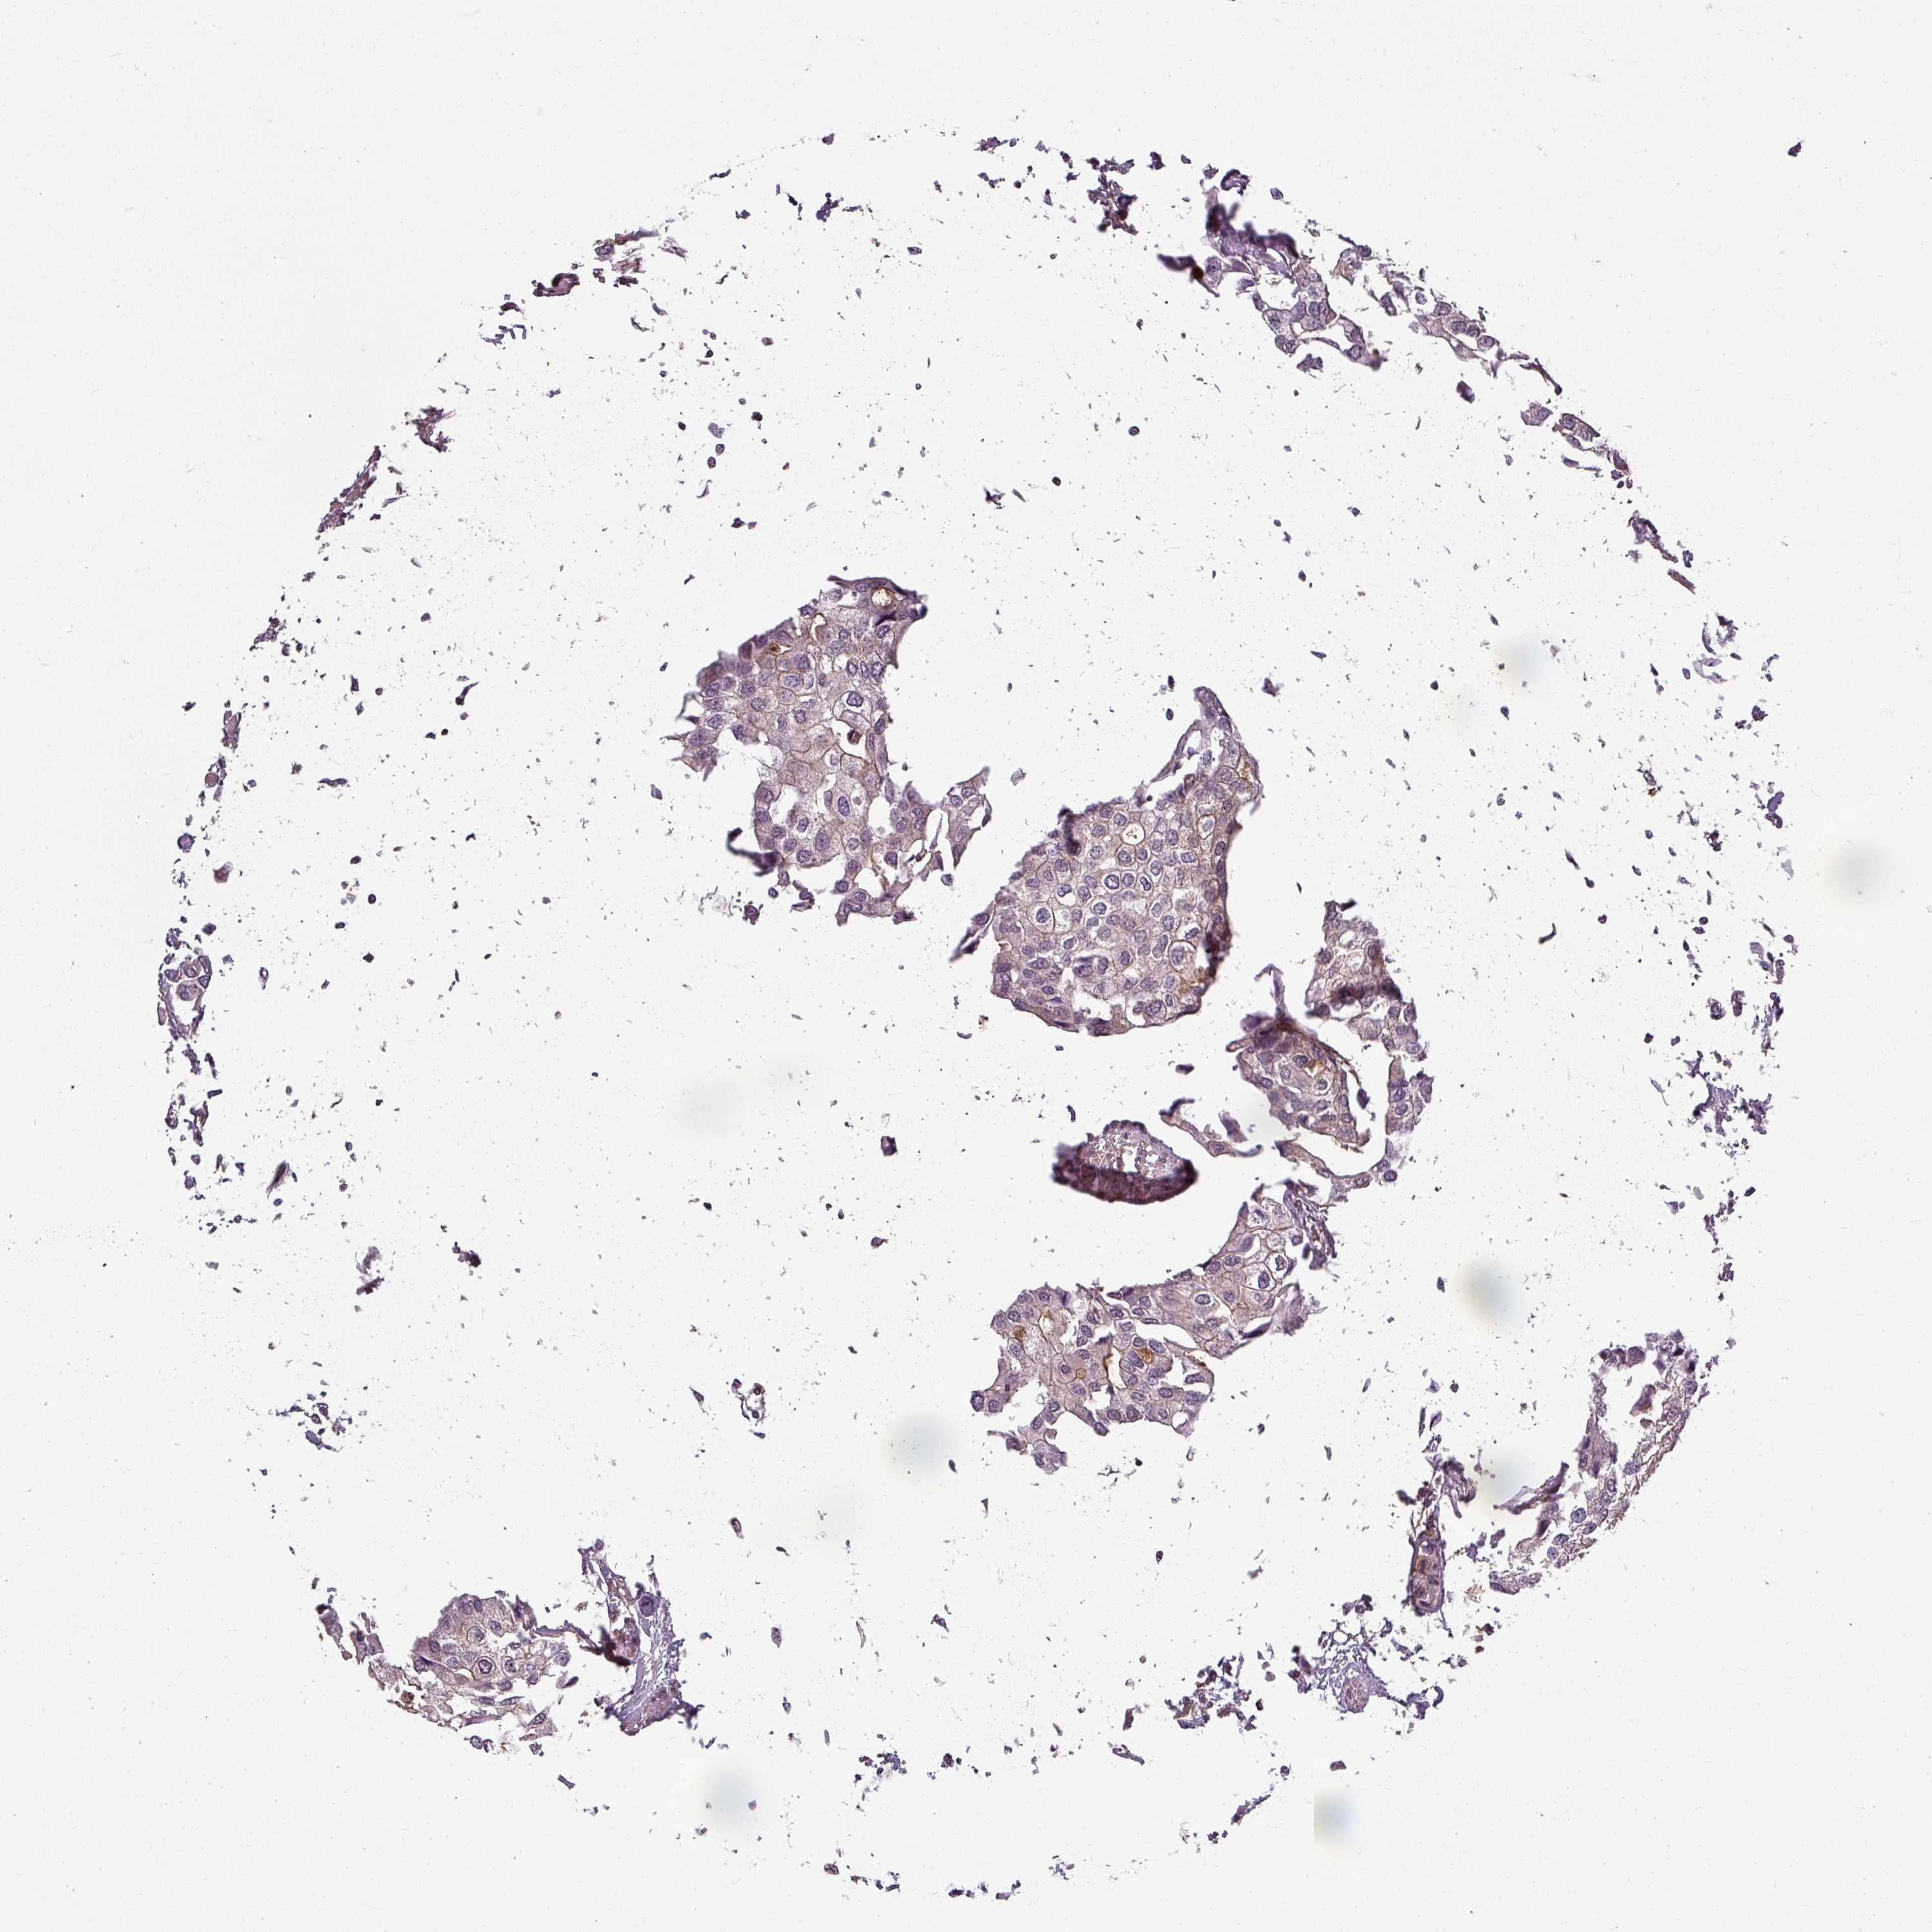

UROTHELIAL CANCER - Protein expressioni

A mouse-over function shows sample information and annotation data. Click on an image to view it in a full screen mode. Samples can be filtered based on level of antibody staining by selecting one or several of the following categories: high, medium, low and not detected. The assay and annotation is described here.

Note that samples used for immunohistochemistry by the Human Protein Atlas do not correspond to samples in the TCGA dataset.

Antibody stainingi

Antibody staining in the annotated cell types in the current human tissue is reported as not detected, low, medium, or high, based on conventional immunohistochemistry profiling in selected tissues. This score is based on the combination of the staining intensity and fraction of stained cells.

Each image is clickable and will lead to virtual microscopy that enables deeper exploration of all samples and also displays staining intensity scores, fraction scores and subcellular localization as well as patient and tissue information for each sample.

Antibody CAB020825

Antibody CAB040557

Urothelial carcinoma, High grade

Urothelial carcinoma, Low grade